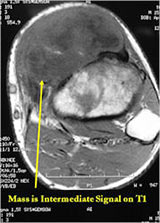

MRI:

- Mass on surface of bone

- Intermediate signal on T1 weighted images and high signal on T2 consistent with cartilage

- Usually no intramedullary invasion but may see slight erosion or saucerization of cortex

- Periosteal reaction evident on MRI as very low signal on T1 and T2 weighted images